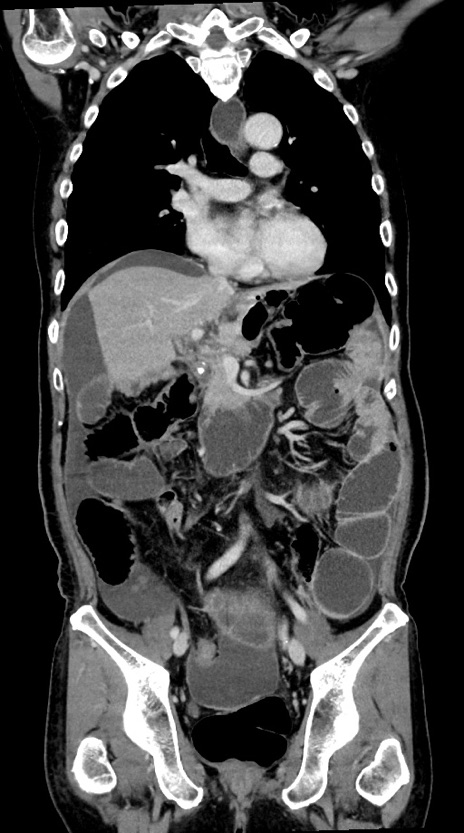

症例28(冠状断像)

【症例】60歳代男性

【主訴】嘔吐

【現病歴】胃癌にて胃全摘後。食思不振が悪化し、夜中に嘔吐することがある。

【既往歴】胃癌、胃全摘、脾摘、胆摘後

【データ】WBC 5900、CRP 10.56